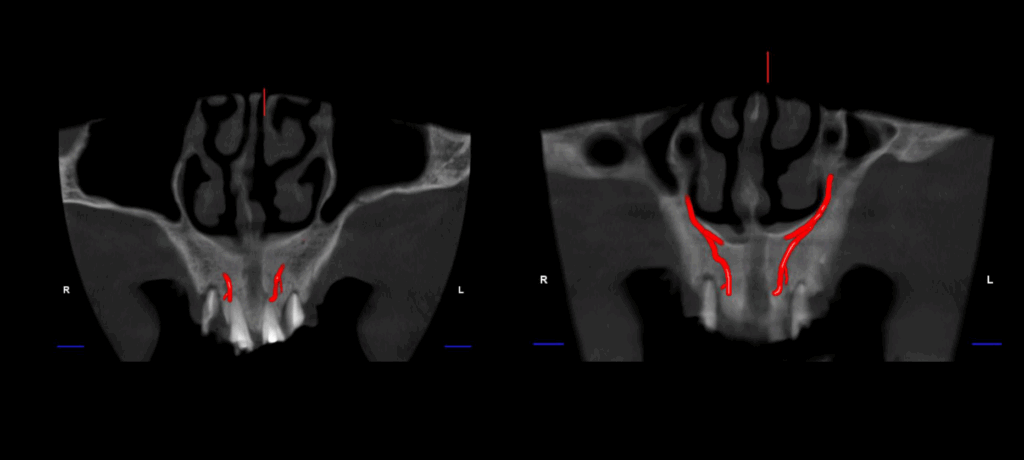

En el estudio complementario mediante tomografía computarizada de haz cónico (TCHC), se identifica la presencia del canalis sinuosus en el maxilar derecho, con trayecto que se dirige hacia la región ósea palatina correspondiente a las piezas 12 y 11. Asimismo, se evidencia un canalis sinuosus en el maxilar izquierdo, que se origina en la pared lateral de la fosa nasal izquierda y se dirige hacia la región ósea palatina y apical de las piezas 21 y 22.

CORTES CORONALES